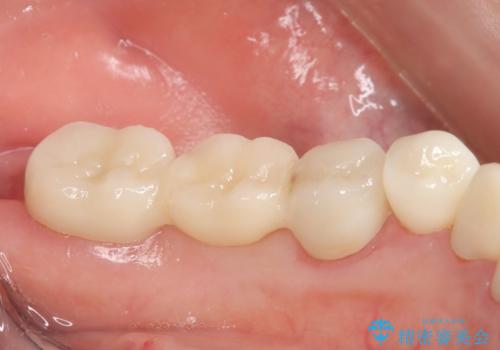

- 左下の銀歯を前の歯に合わせて白くしたいといらっしゃった方の症例です。

前歯部のシェードに合わせ、左下4及び左下567ブリッジをオールセラミッククラウンにて補綴しました。

今回用いたオールセラミッククラウンはジルコニアフレームという白い素材の上にセラミックを盛っているため、審美性が非常に高いのが特徴です。

また、ジルコニアは人工ダイヤモンドの材料にも使われているほど高い強度を持っており、そのためオールセラミッククラウンは審美性だけでなく、奥歯やブリッジの補綴も可能とするクラウンです。